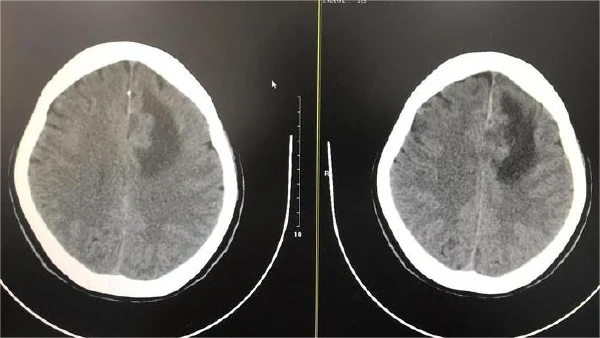

准确的诊断需要结合临床信息、辅助检查结果及医生经验。影像学检查是诊断镰旁顶叶占位病变的关键手段。CT和MRI可以清晰显示病变的大小、位置、形态以及与周围结构的关系。结合增强扫描,可以进一步判断病变的性质,如是良性还是恶性。

影像学检查在分期中起到重要作用。MRI增强扫描不仅可以显示肿瘤的大小和位置,还能判断肿瘤与周围脑组织和血管的关系,以及有无脑水肿、脑疝等并发症。